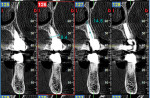

One year postoperatively, clinical examination noted healthy keratinized soft tissue covering the grafted site (Figure 6). A CBCT was taken to evaluate the osseous graft healing and the graft's incorporation to the host bone and determine if adequate volume of bone was present to allow implant placement (Figure 7). The scan demonstrated a fully clear sinus and sufficient bone to permit placement of two implants. Following local anesthetic administration a crestal incision was made and the crest was exposed to reveal dense bone with no visibly identifiable graft particles. An initial osteotomy was created in the second premolar and first molar sites with guided surgery. To achieve desired increased implant length, a crestal sinus augmentation was planned, and to improve bone quality surrounding the implant to be placed, an osseodensification protocol was used.30 Crestal sinus augmentation was performed with a combination of piezosurgery (Mectron, dental.mectron.us) and osseodensification (Versah, versah.com). These proprietary drills were also used to increase the density of the bone and improve osseointegration simultaneously.31

A 97.5-year-old healthy female patient presented for an emergency appointment with a fractured maxillary left first premolar (tooth No. 12). Examination noted the tooth was missing the coronal portion and was level with the gingival margin. A periapical radiograph was taken, and the tooth was deemed nonrestorable due to the degree of missing tooth structure (Figure 9). A CBCT cross-section view of the affected tooth demonstrated the dimensions of the space and an intact buccal aspect of the ridge (Figure 10). Treatment options were discussed with the patient that included extraction of the remaining root followed by either preparation of the teeth mesial and distal to the space and placement of a fixed partial denture or placement of an implant and restoration with a crown. The patient said she did not want her "teeth cut down" and selected the implant treatment option.